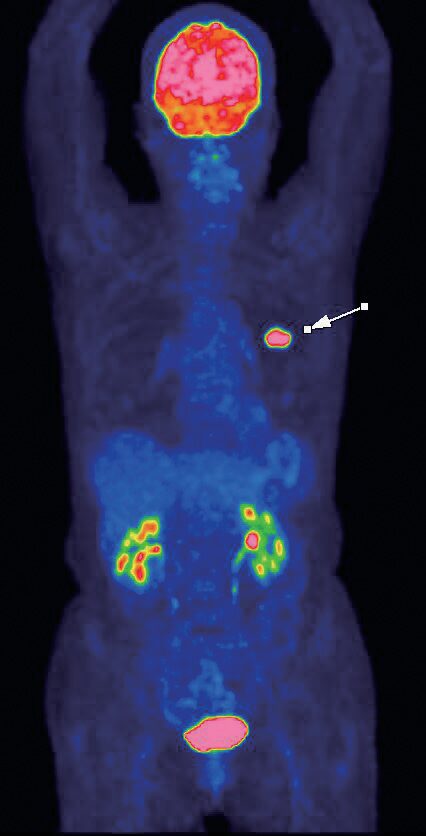

2026(令和8)年1月5日に、魚住クリニックから名称を変更した「あかりPET画像診断クリニック」。その名の通りPET(ペット)画像診断を専門とする医療機関だ。がんの早期発見につながるとして近年注目されているPET画像診断。もともとがん細胞は、健康な細胞と比べ、ブドウ糖を取り込みやすい性質がある。この性質に着目し、糖を含んだ薬剤を注射、全身のブドウ糖の代謝活動をPETカメラで画像化する。体内のブドウ糖の状態を見ることで、がん細胞の場所や性質、活動状況まで詳しく診断できる。

がんの大きさ・形を映し出すCTやMRIに対し、PET検査はがん細胞の活動性まで調べられるのが特長。良性腫瘍との鑑別や治療によって死滅しつつあるがん細胞、逆に今後大きくなりそうながん細胞などを見分けることができる。またCTとPETを組み合わせるとさらに精度は上がり、これまで見つけられなかったがんの発見や転移・再発の診断が可能になる。検査は問診後、薬剤を注射し、薬剤が浸透するまで1時間ほど安静待機、その後PETカメラで撮影する流れ。痛みはなく着衣のままで検査でき、一度の検査で全身の診断ができる。検査終了後はすぐ通常の生活に戻れるなど患者にとってメリットも多い。